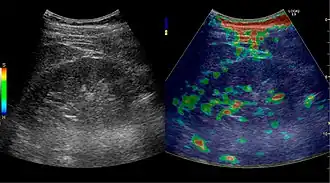

Solid malignant tumors in the kidney do not exhibit specific enhancement patterns like some liver lesions, and no valid enhancement criteria between benign and malignant renal lesions have been proposed. However, CEUS is used in some patients after ablation of renal cell carcinoma to evaluate contrast uptake in the treated area (Figure 30).

Figure 31. Unspecific cortical lesion on CT is confirmed cystic and benign with contrast-enhanced ultrasound (CEUS) using image fusion.[1] -